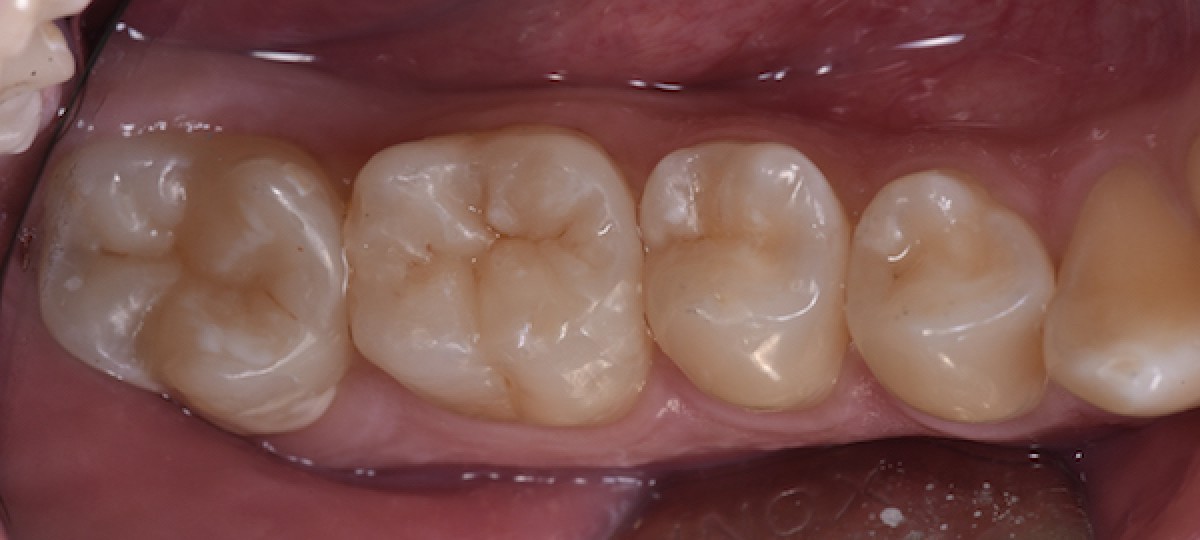

Seven days later, polishing and color check (Fig. 14)

Four months follow-up (Fig.15)